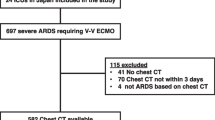

During the study period, 632 patients were assessed for eligibility. After excluding those who underwent exclusively NIV or with missing data, the original study enrolled a total of 470 patients. Of these, 139 had a CT scan performed within ± 3 days from orotracheal intubation and were therefore included in the final analysis; supplement Fig. 1 shows the flow of the patients throughout the study.